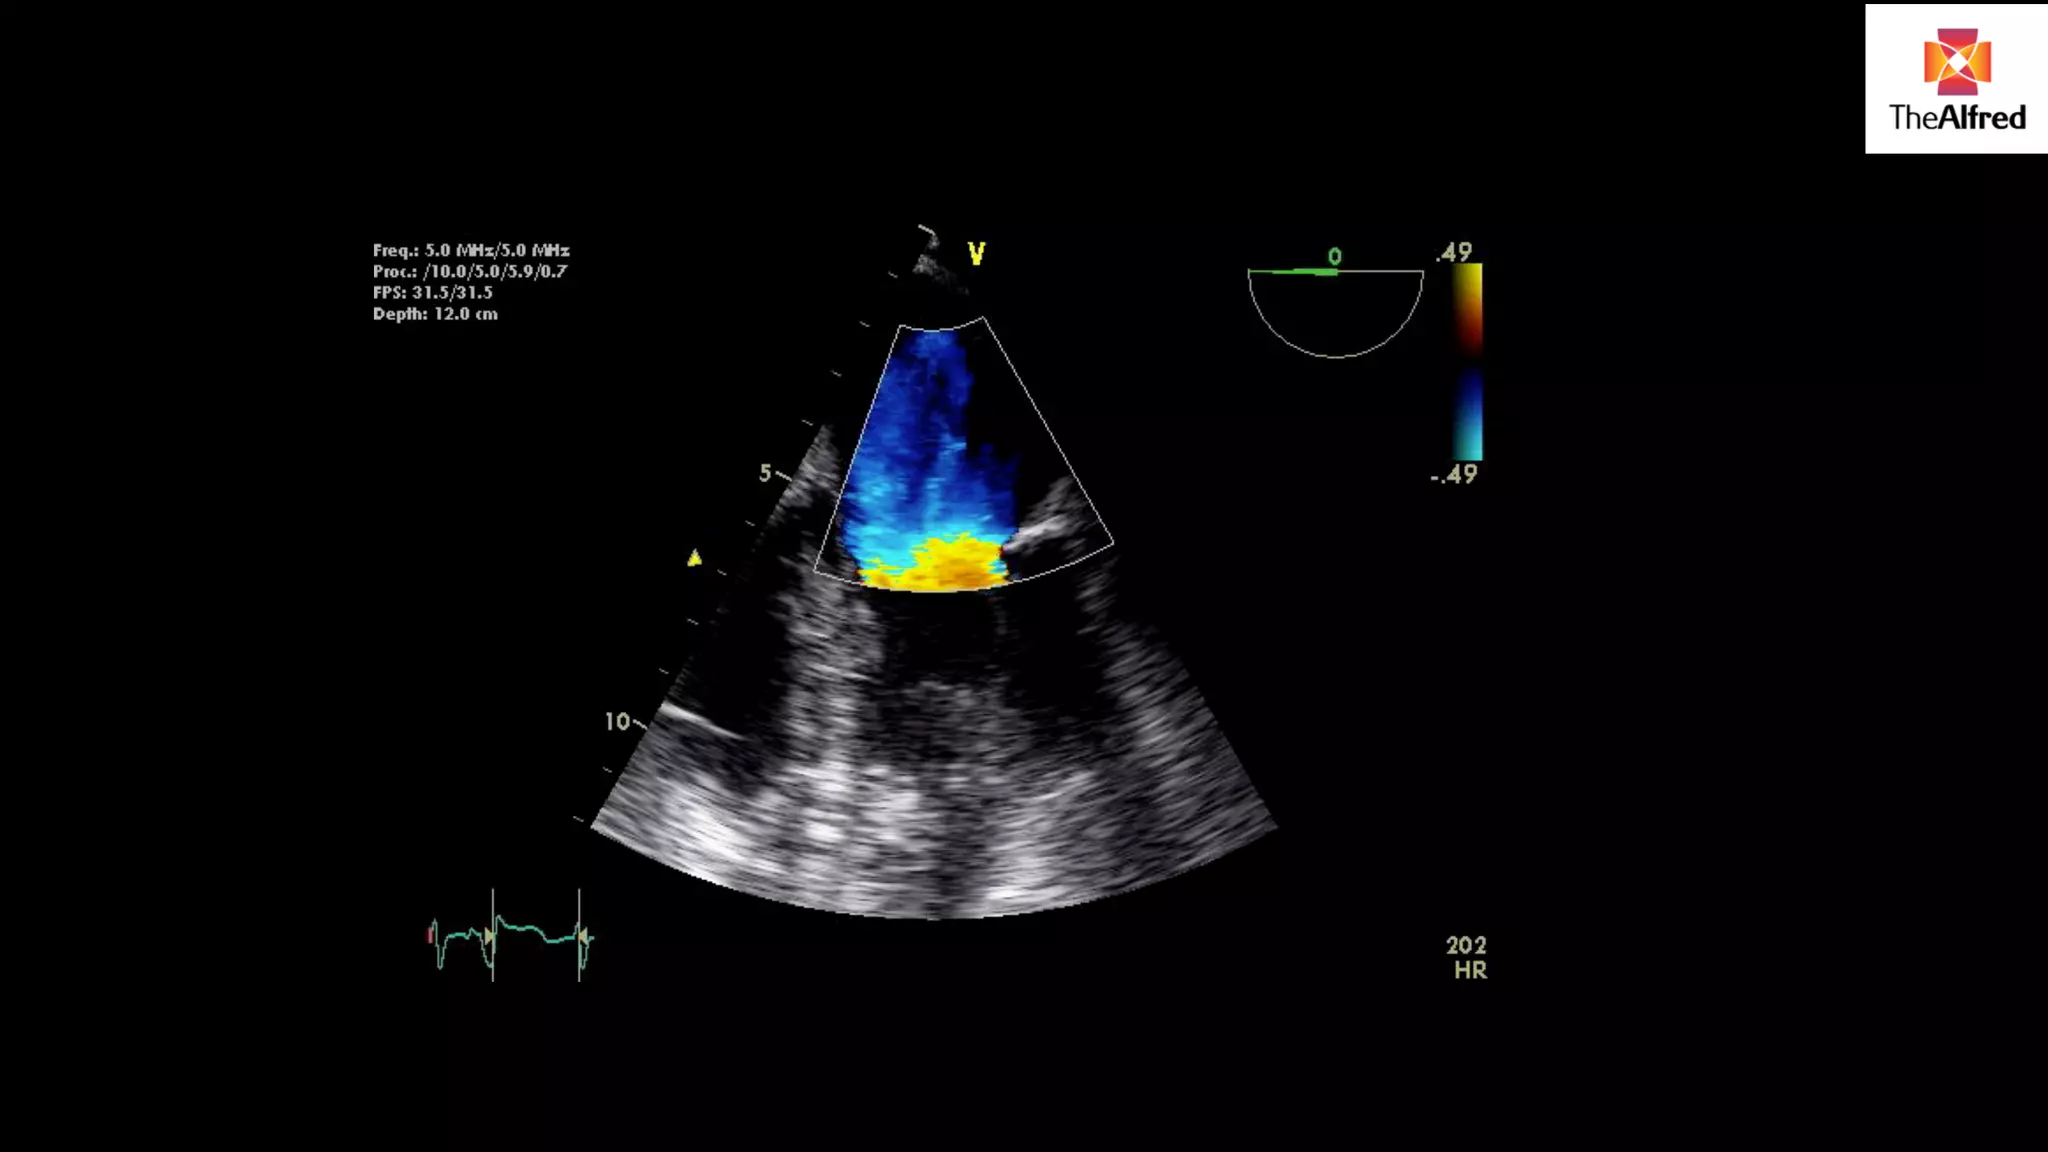

5 chamber

view

3 chamber

LVOT method Assumesthe LVOT is a cylinder We can measure the VTI of blood flow in the LVOT by placing a pulse wave doppler gate in LVOT This gives us the LVOT VTI

USE VIEW WITHTHE BEST DOPPLER LINE UP- DIFFERENT FOR DIFFERENT PATIENTS 5 chamber view 3 chamber view